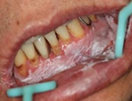

后来,还是在二年前一家医院结识的病友的介绍下,才辗转又在广州找到广州市南粤医药研究所附属医院口腔黏膜专科,本没想过会有太好的效果,随便治吧,反正都这样了。后来薛镇宇主任给张鑫采用了医院独创的“中西医四联疗法”的特色疗法,中西医结合、全身用药与局部治疗结合进行治疗,一周过后,唇炎病情有了明显好转。张鑫高兴地来到医院复查,他跟医生说多年来自己第一次如此开心,治疗多年的疾病终于见到效果了。经过2个月治疗,最终治好了困扰张鑫多年的唇炎。

医生也高兴地看到,张鑫现在也能和正常人一样,可以笑了。

张鑫治疗后